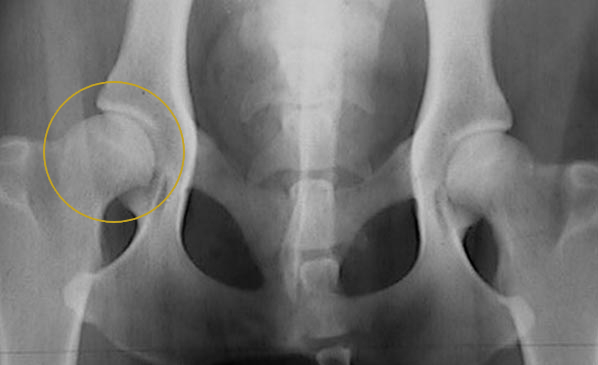

Aún así, insistimos en realizar radiografía (que se hizo sin sedación) y obtuvimos el primer diagnóstico: displasia bilateral leve, estando más afectada la cadera derecha que la izquierda, pero (en teoría) nada especialmente preocupante.

Volvimos al veterinario a hacer radiografía (de nuevo sin sedación) y esto fue lo que se vio:

Aparentemente no difería tanto de la primera, pero nos empeñamos en que lo viese un traumatólogo y que le hiciesen las radiografías adecuadas con sedación.

Hacer radiografía sin sedación a un perro para detectar o descartar displasia, puede servir como primera prueba pero poco más. Los resultados que arroje van a ser poco específicos, dado que para poder posicionar al perro en la postura adecuada se le tiene que poner en una postura antinatural y por lo tanto se le causa dolor: por tanto, si el perro no está dormido, no dejará que lo posiciones como corresponde y la imagen que se realice será aproximada.

Por eso es tan importante hacer un estudio radiológico con sedación para detectar la gravedad de una displasia de cadera.

Así que esto fue lo que vimos en una de las 4 radiografías realizadas. En el lado izquierdo está la radiografía buena (con el perro sedado), y en el lado derecho ponemos al lado la radiografía previa sin sedación para que veas cómo cambia el diagnóstico cuando el perro está en la posición correcta:

El diagnóstico es bastante más feo. Pirlo tiene displasia grave de cadera. La cabeza del fémur apenas entra en el acetábulo unos milímetros, en el caso de la pata derecha. Esto quiere decir que al caminar, la cabeza del fémur posiblemente se salga por completo de la cavidad y cuando eso sucede, el perro cojea. Al parar, se recoloca la pata y deja de cojear hasta que vuelve a suceder lo mismo tras unos minutos caminando.